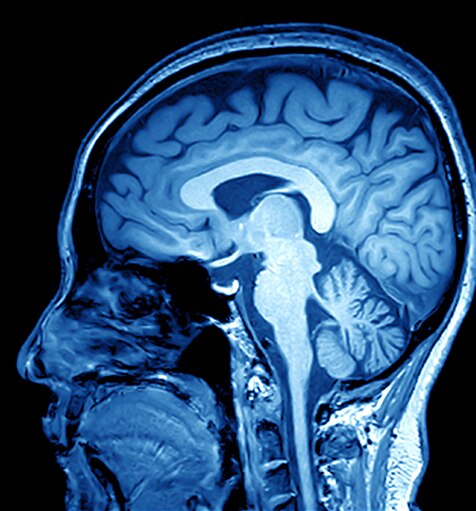

MRI (Magnetic Resonance Imaging) is a non-invasive scanning technology that produces cross sectional images of the body. It is used in a range of medical fields including: musculoskeletal, gastrointestinal, oncology, cardiovascular and neuroimaging. MRI scanning can differentiate soft tissue structures in any plane making it an invaluable diagnostic tool.

MRI scanners generate a strong magnetic field that is used in conjunction with radiofrequency currents to stimulate specific molecules in the body.

The behaviour of the molecules can be used to generate a three-dimensional image of body tissues. Example MRI images are shown below: